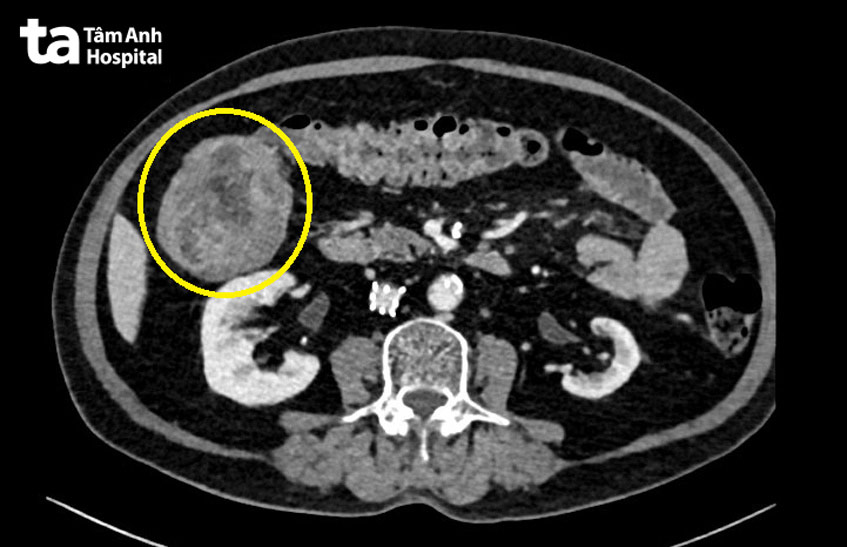

Kết quả cho thấy một khối u lớn ở đại tràng phải, kích thước hơn 5cm, gây bít lòng, khiến ống soi không thể qua. Khối u chính là nguyên nhân gây ra tình trạng đi tiểu ra máu ở người bệnh. Bên cạnh đó, do tác dụng phụ của thuốc kháng đông khiến cho tình trạng bệnh ở đường tiêu hóa diễn ra nặng và rõ ràng hơn. Do đó, người bệnh cần được phẫu thuật sớm.